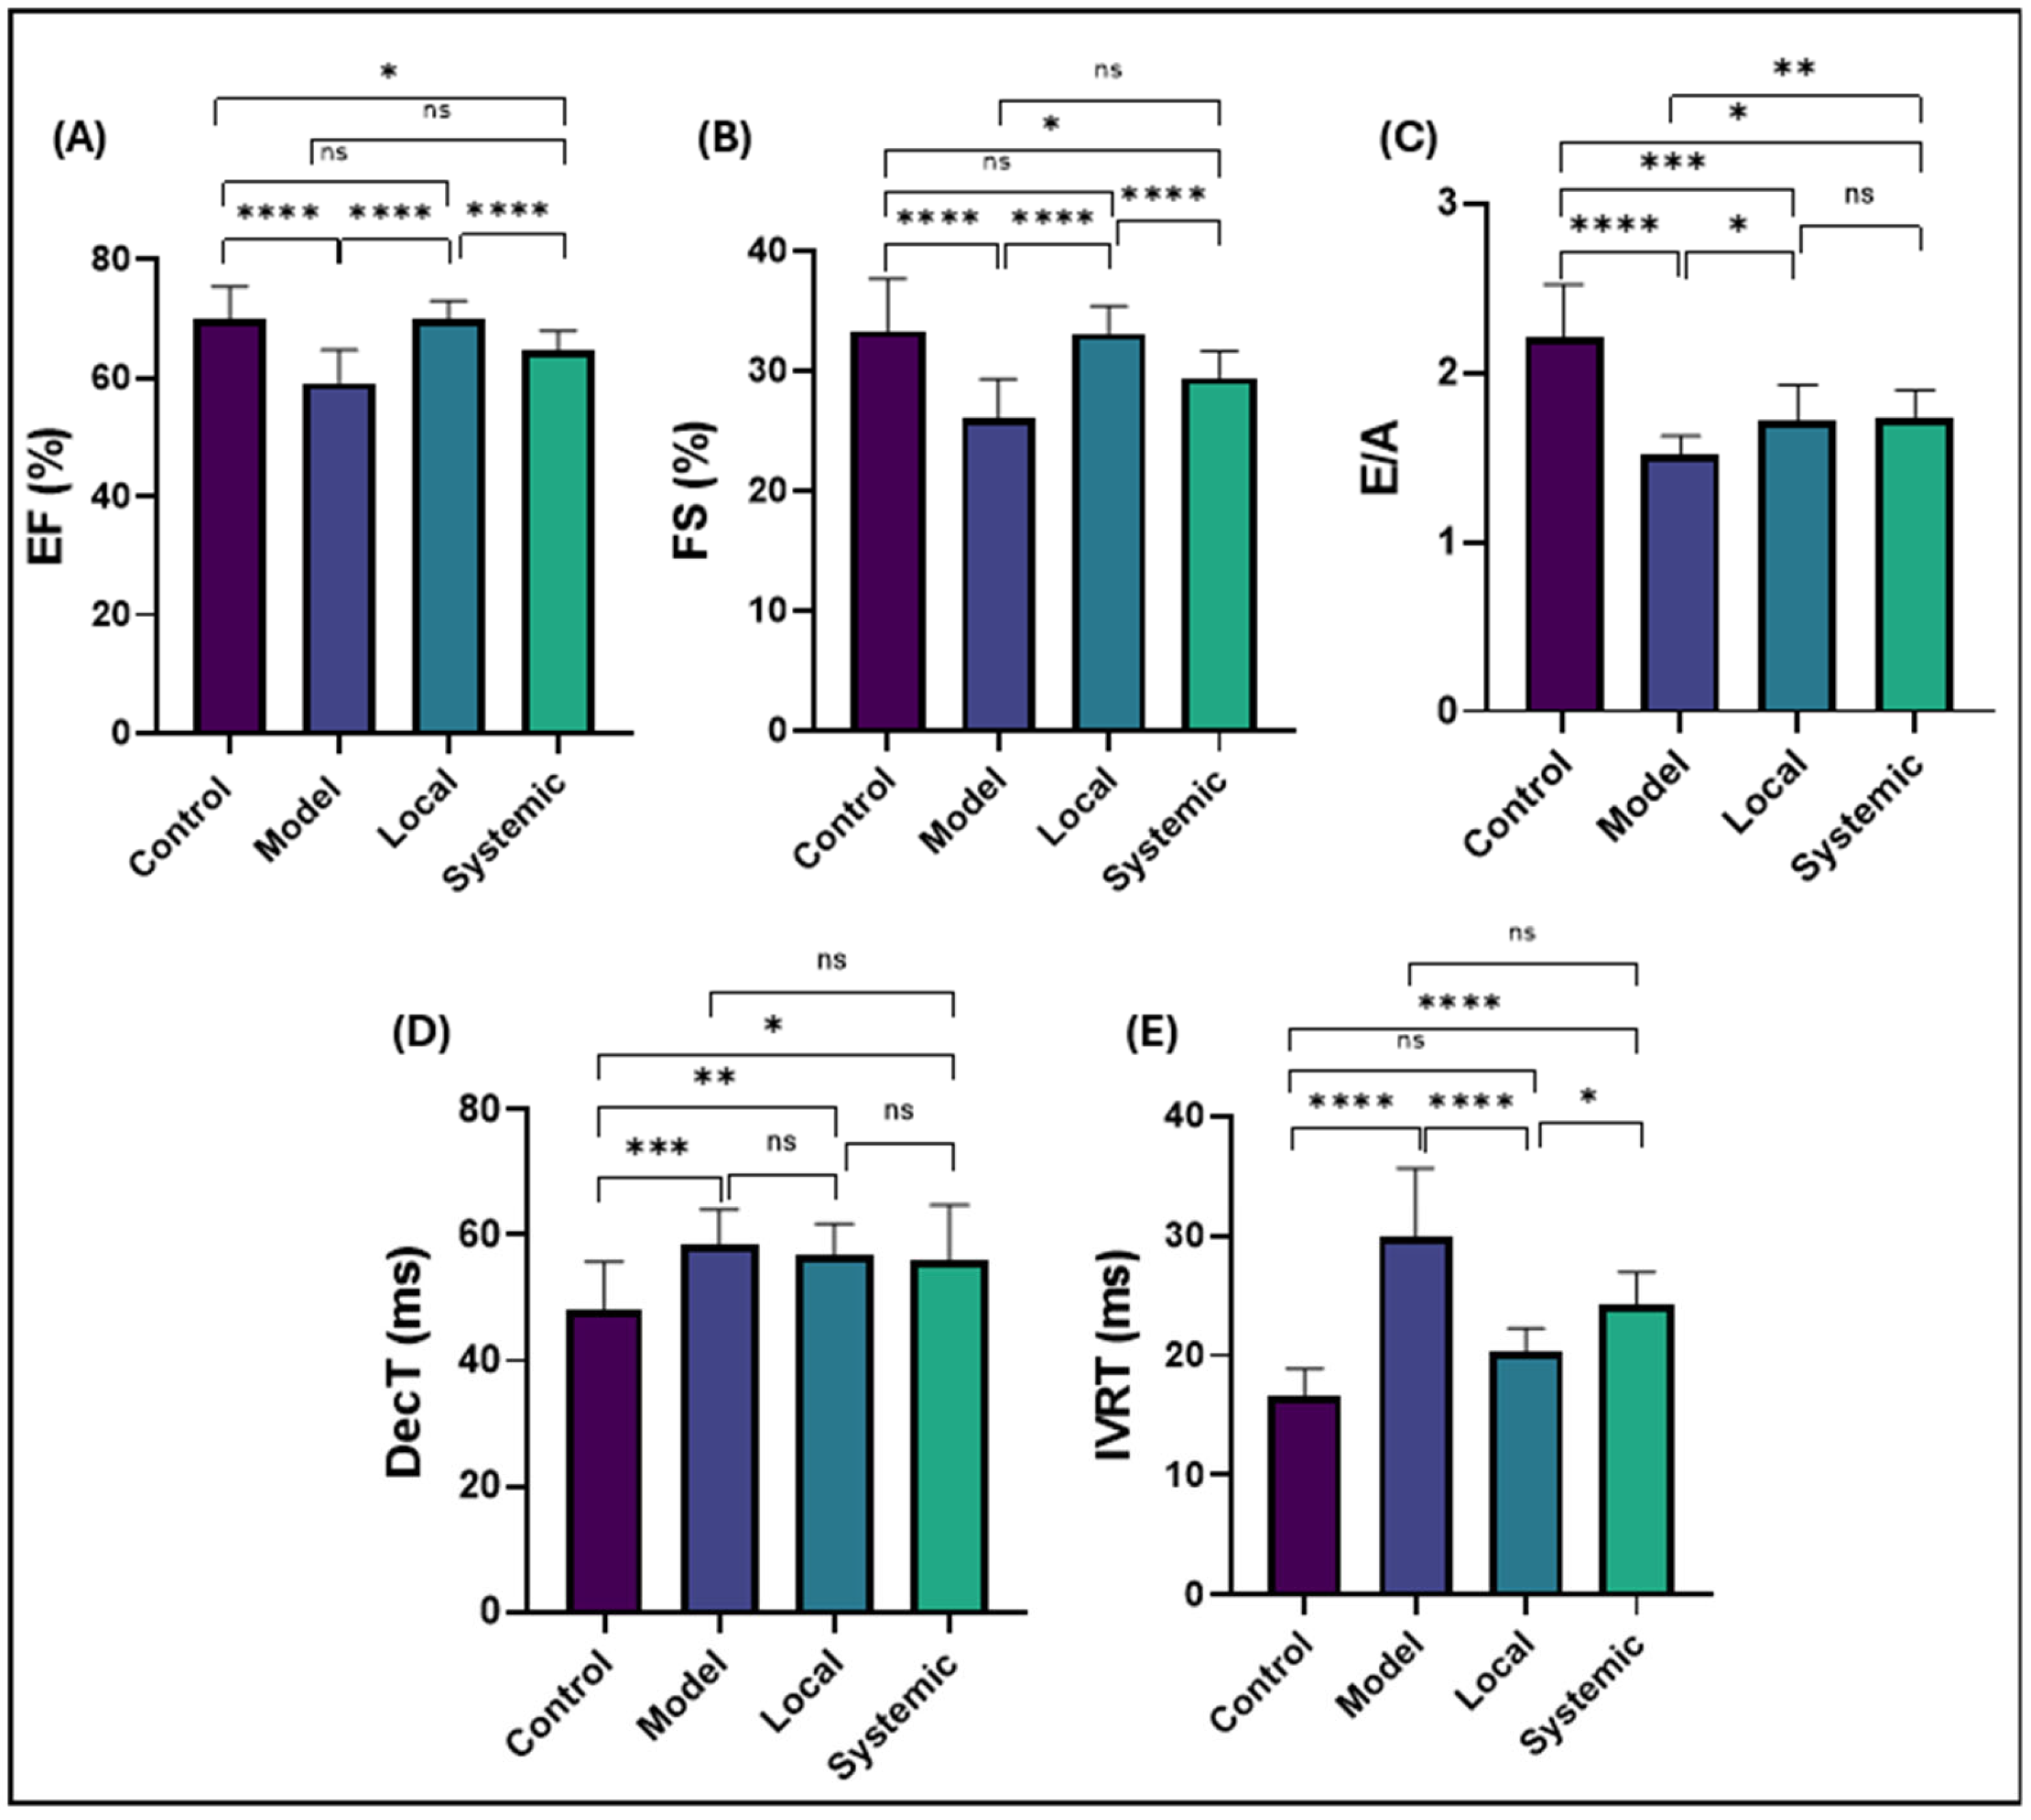

2.6. Conventional Echocardiographic Findings

4.9. Conventional Echocardiography